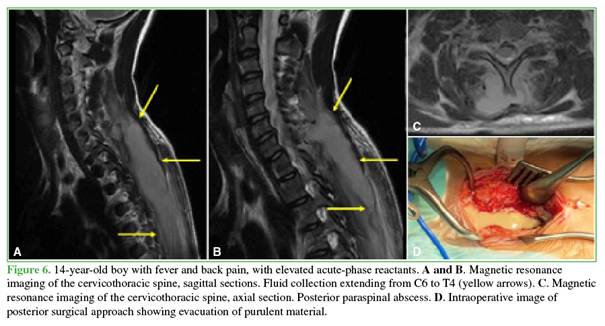

Staphylococcus aureus was isolated in

seven patients (p = 0.001), including four cases of MRSA and three of MSSA (Figures 3-6).

On

computed tomography, bone lesions exhibited a lytic or mottled appearance, with